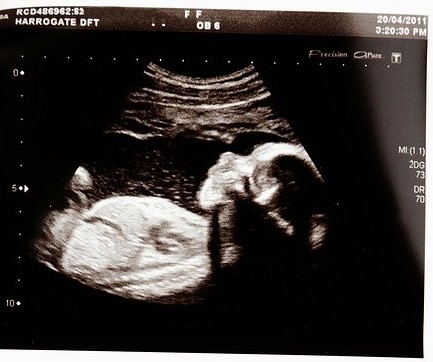

Il sangue della madre può trasferirlo nel sangue fetale. In pratica, la madre respira, l’ossigeno arriva nel suo sangue, qui è legato dall’emoglobina (proteina nei globuli rossi, cellule sanguigne). Ora, in corrispondenza dell’organo placenta, i vasi sanguigni del feto scorrono accanto a quelli materni, senza scambio di globuli. L’O2 abbandona i globuli rossi materni, attraversa le pareti dei vasi e lega quelli del feto, così che possa riceverlo, fino a quando non nascerà e potrà respirare da solo.